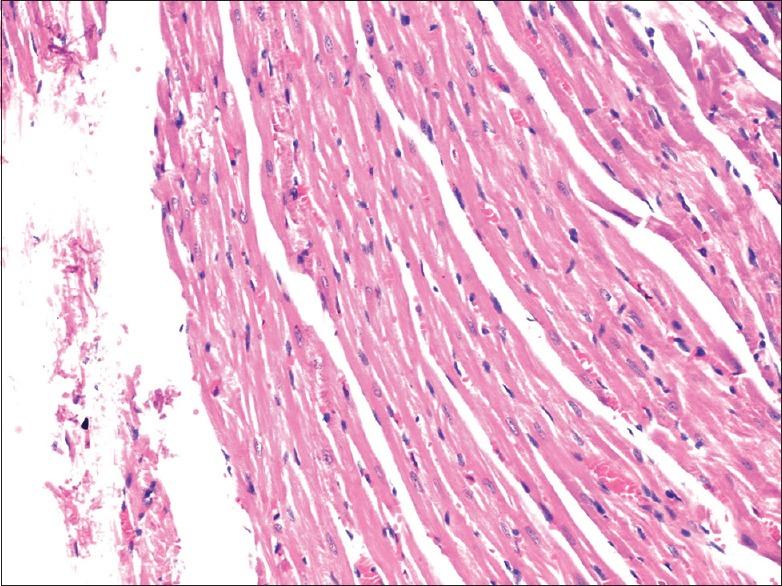

preparation was administered to male and female Wistar rats for ninety consecutive days at 2.7, 13.5, and 27 mg/kg body weight. All relevant biochemical and hematological changes were observed. At termination, all the rats were sacrificed and necropsy was performed. Histopathological evaluation was also performed.

There was a significant increase in high-dose group kidney weight of both sexes which could not be correlated with histopathology findings and serum biochemistry. Therefore, the change was not considered as an adverse effect.

以2.7、13.5和27mg/kg体重的剂量连续90天给予雄性和雌性Wistar大鼠。观察所有相关的生化和血液学变化。实验结束时,处死所有大鼠并进行尸检。还进行了组织病理学评估。

高剂量组两性大鼠的肾脏重量均显著增加,但这与组织病理学结果和血清生化指标无关。因此,该变化不被视为有害效应。